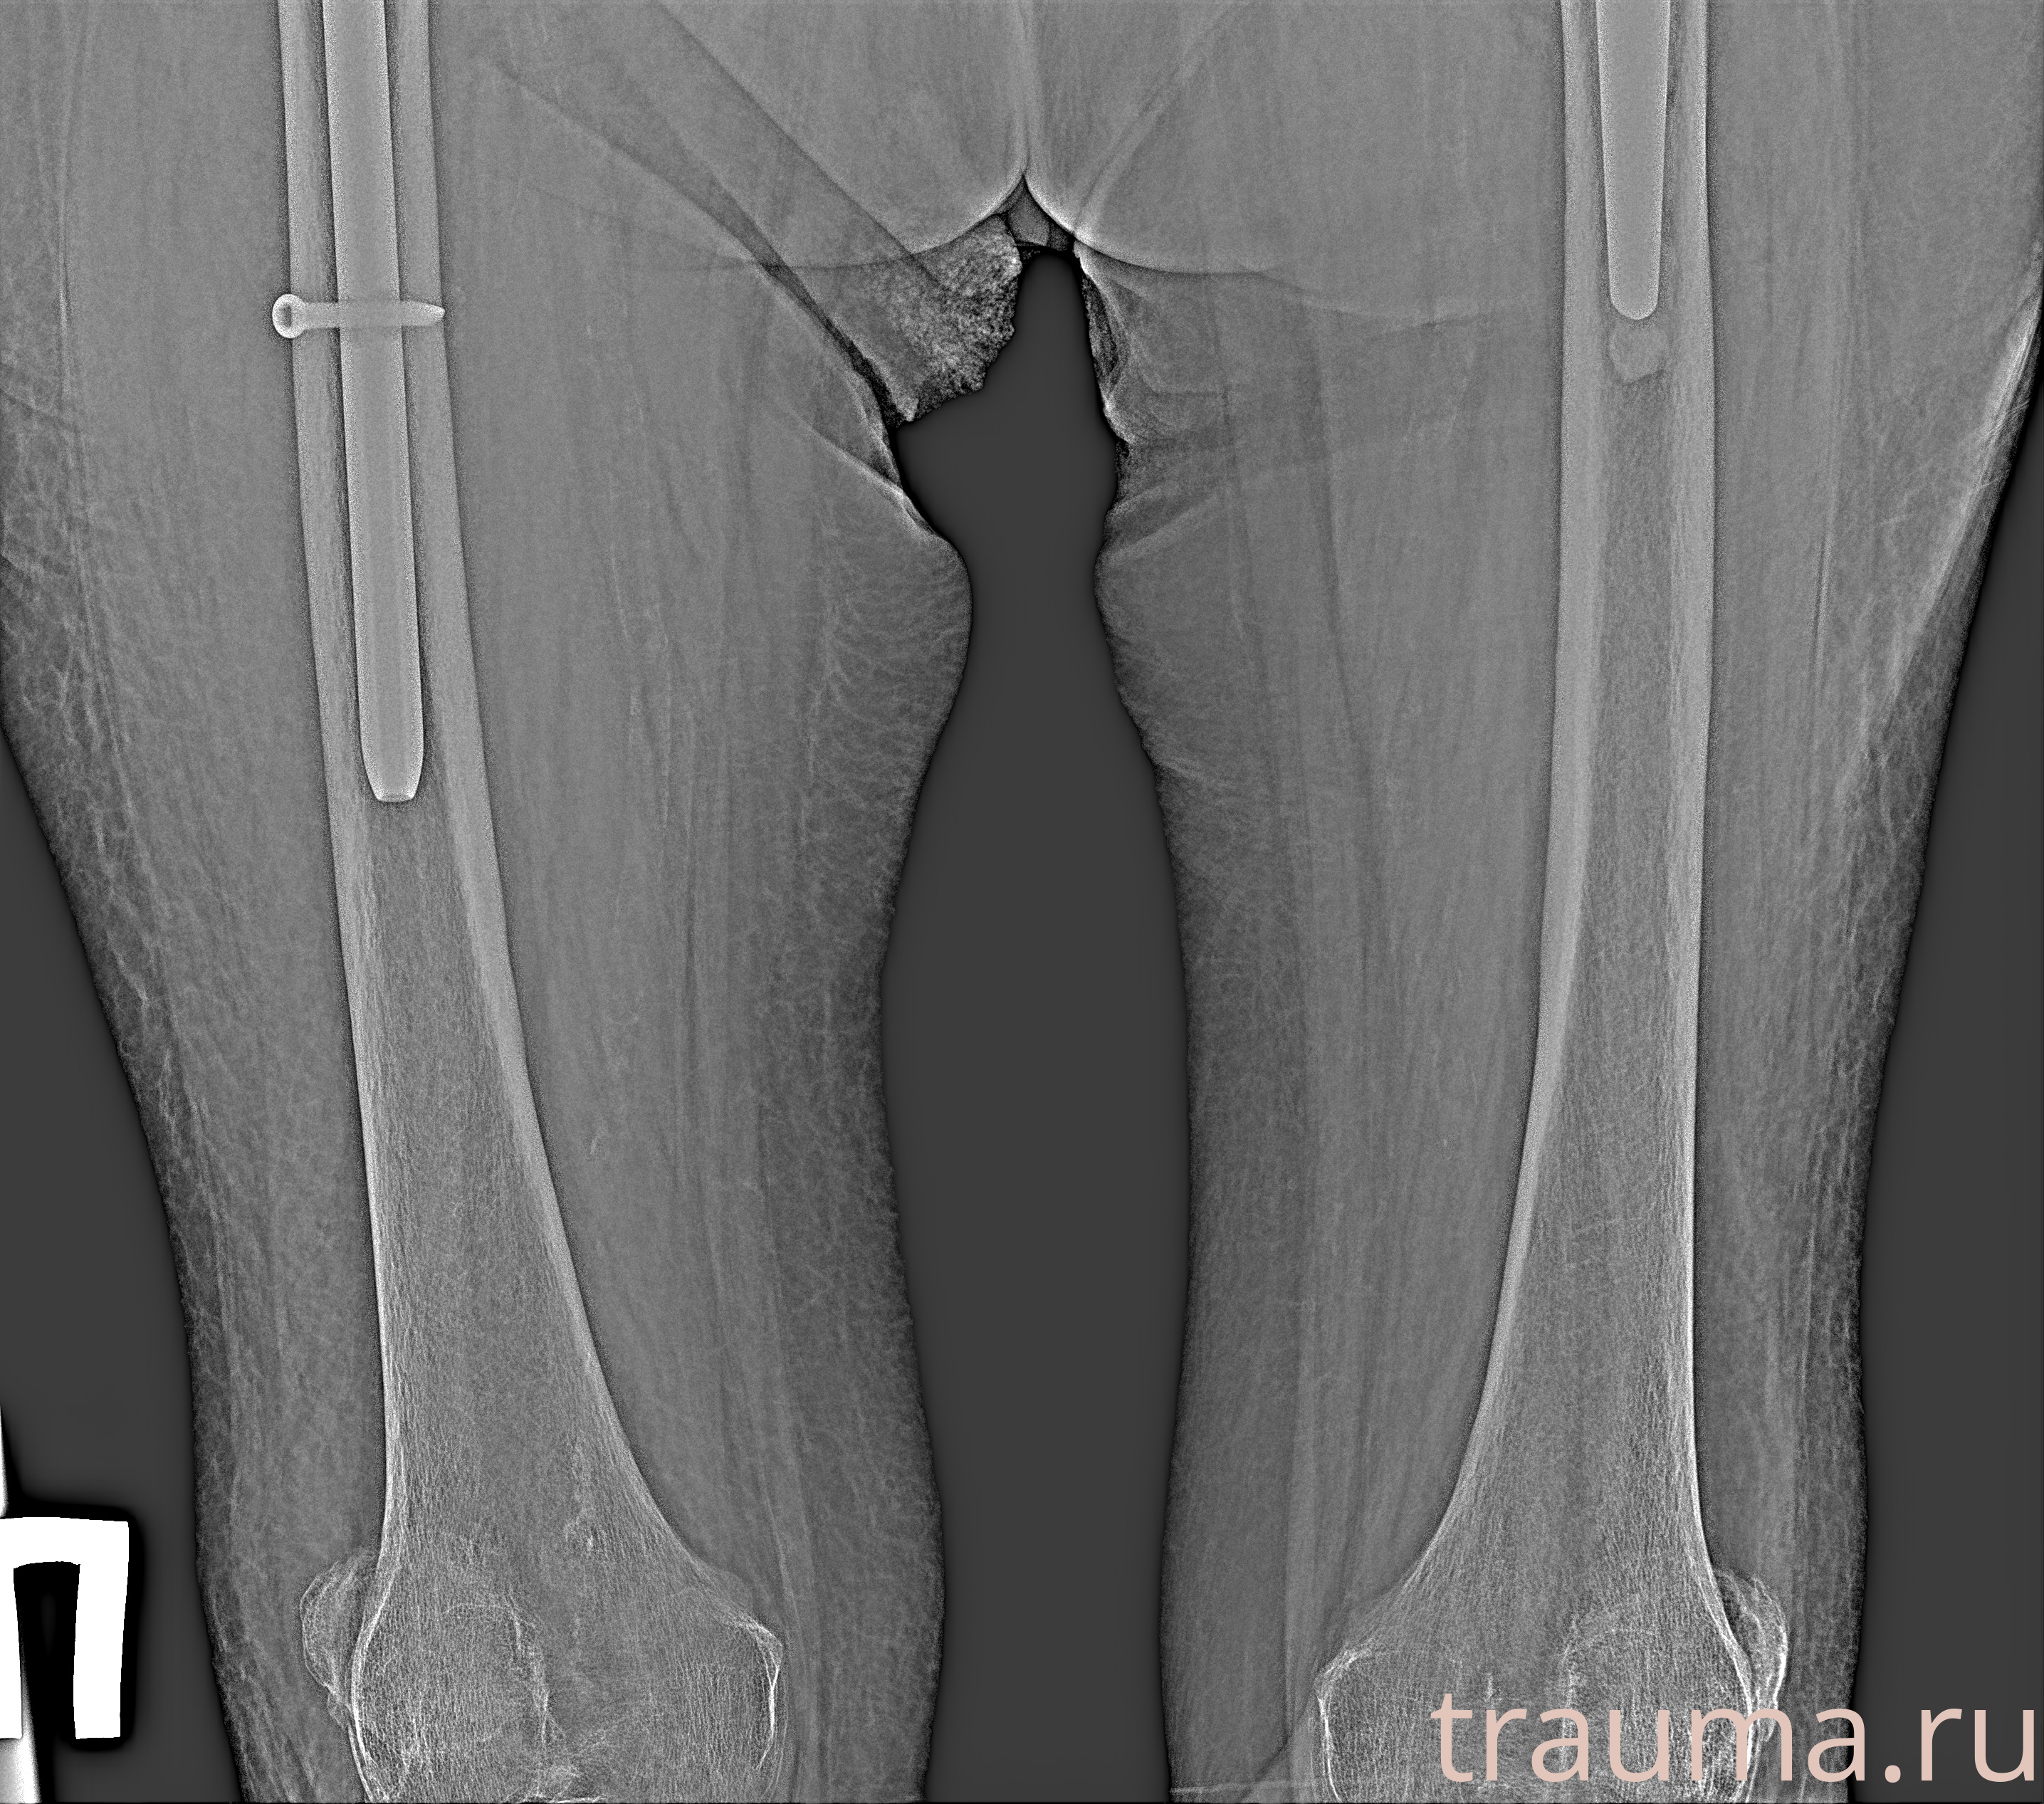

Рентгенограммы

Рентген на дому: по вашему адресу приезжает врач-рентгенолог, травматолог-ортопед с мобильным рентгеновским аппаратом, проводит диагностику травмы или заболевания, делает необходимые рентгенограммы, дает рекомендации по дальнейшему лечению. Получить качественные снимки в домашних условиях возможно благодаря уникальной методике, разработанной МосРентген Центром для института  Склифосовского